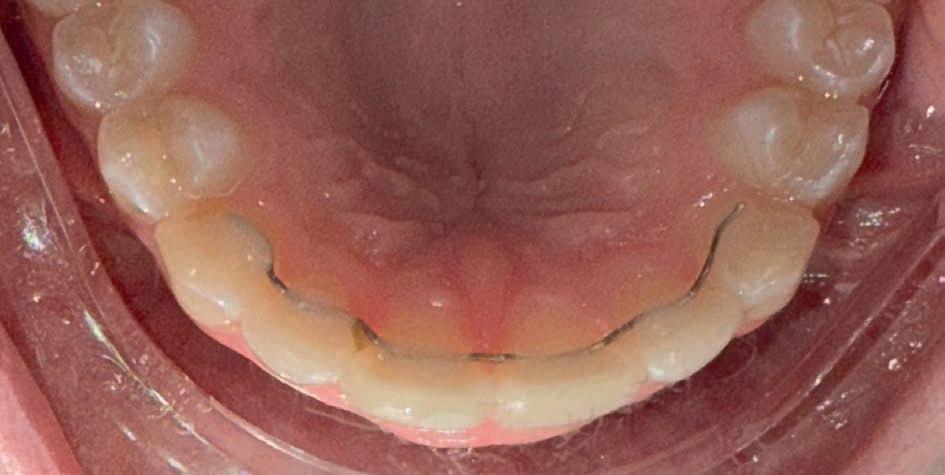

Casus in Proces

Patiënt Sonnie presenteerde zich met ernstig ruimtegebrek ter hoogte van de 13 en 44 en een kruisbeet aan de zijde van de 15 en 14. De 13 was ectostematisch gepositioneerd, waardoor extractie aanvankelijk als mogelijke behandeloptie werd overwogen.

Door een combinatie van verbreding en het inzetten van een D-gainer wordt de benodigde ruimte gecreeerd om alle elementen correct in de tandboog te positioneren, waardoor extracties kunnen worden vermeden. De behandeling zal binnen twee jaar worden afgerond; het eindresultaat wordt gedeeld in editie 2 van ons magazine.

Start behandeling

Midden behandeling

Laatste fase